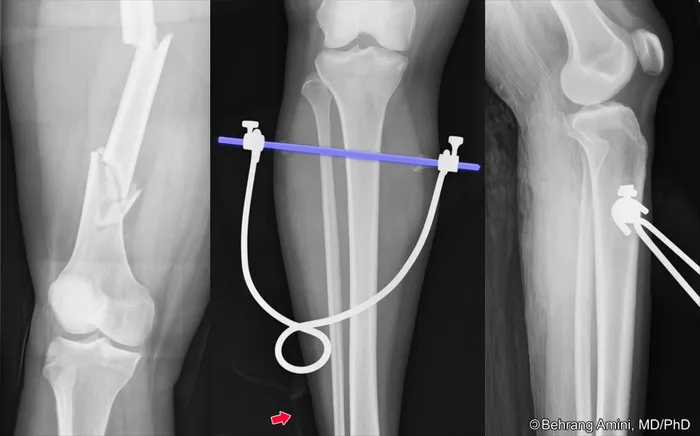

You may have seen pictures of people lying in bed with the cast on a broken leg, and ropes from the cast going to a pulley at the end of the bed with weights to keep the bones aligned while the leg healed.[3]

Of course, to do this Doctor Cook had to place a pin through the tibia.[4]

Usually setting the pin requires a doctor, at least one nurse, a small mountain of supplies and equipment in an operating suite, and, in Doctor Cook's mid-career, cost some $1000. The good doctor, in his never-ending quest to solve his patient's problems at a cost they could pay, realized he could insert the blunt end of the orthopedic pin into his electric drill, douse the pin with alcohol, light the alcohol to sterilize the pin, cool the pin in a surgical antiseptic, inject a local anesthetic into the skin and area around the bone, and drill the pin through the bone in the patient's room. He reports that he always succeeded with this and never caused an infection.[5] These days, any hospital attorney would suffer a cardiac arrest at the mere suggestion.

[3] https://www2.aofoundation.org/wps/portal/!ut/p/c0/04_SB8K8xLLM9MSSzPy8xBz9CP0os3hng7BARydDRwN3QwMDA08zTzdvvxBjIwN_I_2CbEdFADiM_QM!/?basicTechnique=Femur%20shaft%20fracture%20management%20with%20minimal%20resources&segment=Shaft&bone=Femur&showPage=redfix

[4] http://roentgenrayreader.blogspot.com/2012/01/lower-limb-skeletal-traction-proximal.html